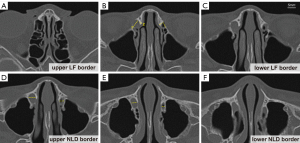

The measured parameters included LF height, LF width, frontal process thickness, NLD height, the narrowest NLD width, and upper NLD width. To help evaluate the parameters, six axial levels were defined on the CT images. The upper LF border corresponded to the uppermost axial level of the LF (Figure 2A). The level immediately superior to the lower LF border was used to measure LF width and frontal process thickness (Figure 2B). The lower LF border represented the last axial level before the appearance of the complete ring of the NLD (Figure 2C). The upper NLD border indicated the first axial level showing the complete ring of the NLD (Figure 2D). The narrowest NLD width was measured at the axial level where the duct exhibited its smallest diameter (Figure 2E). The lower NLD border corresponded to the section where the NLD opens into the nasal cavity (Figure 2F) (22).

The LF height refers to the distance between the upper LF border and the lower LF border (Figure 2A,2C). This measurement was calculated by multiplying the number of sections by 0.75 mm, as reported in previous studies (22,23). In addition, the LF width was measured as the distance between the anterior extent of the LF and the posterior lacrimal crest (Figure 2B, line 1), whereas the frontal process thickness was determined at the midpoint between the anterior extent of the LF and the lacrimomaxillary suture in the level prior to the lower LF border (Figure 2B, line 2) (20). Furthermore, the NLD height was defined as the distance between the upper NLD border and the lower NLD border (Figure 2D,2F), also calculated by multiplying the number of sections by 0.75 mm. Finally, the narrowest NLD width and the upper NLD width were both determined as the transverse distances of the NLD. Specifically, the narrowest NLD width was obtained at the section with the smallest diameter of the NLD (Figure 2E), whereas the upper NLD width was measured at the upper NLD border (Figure 2D) (24).